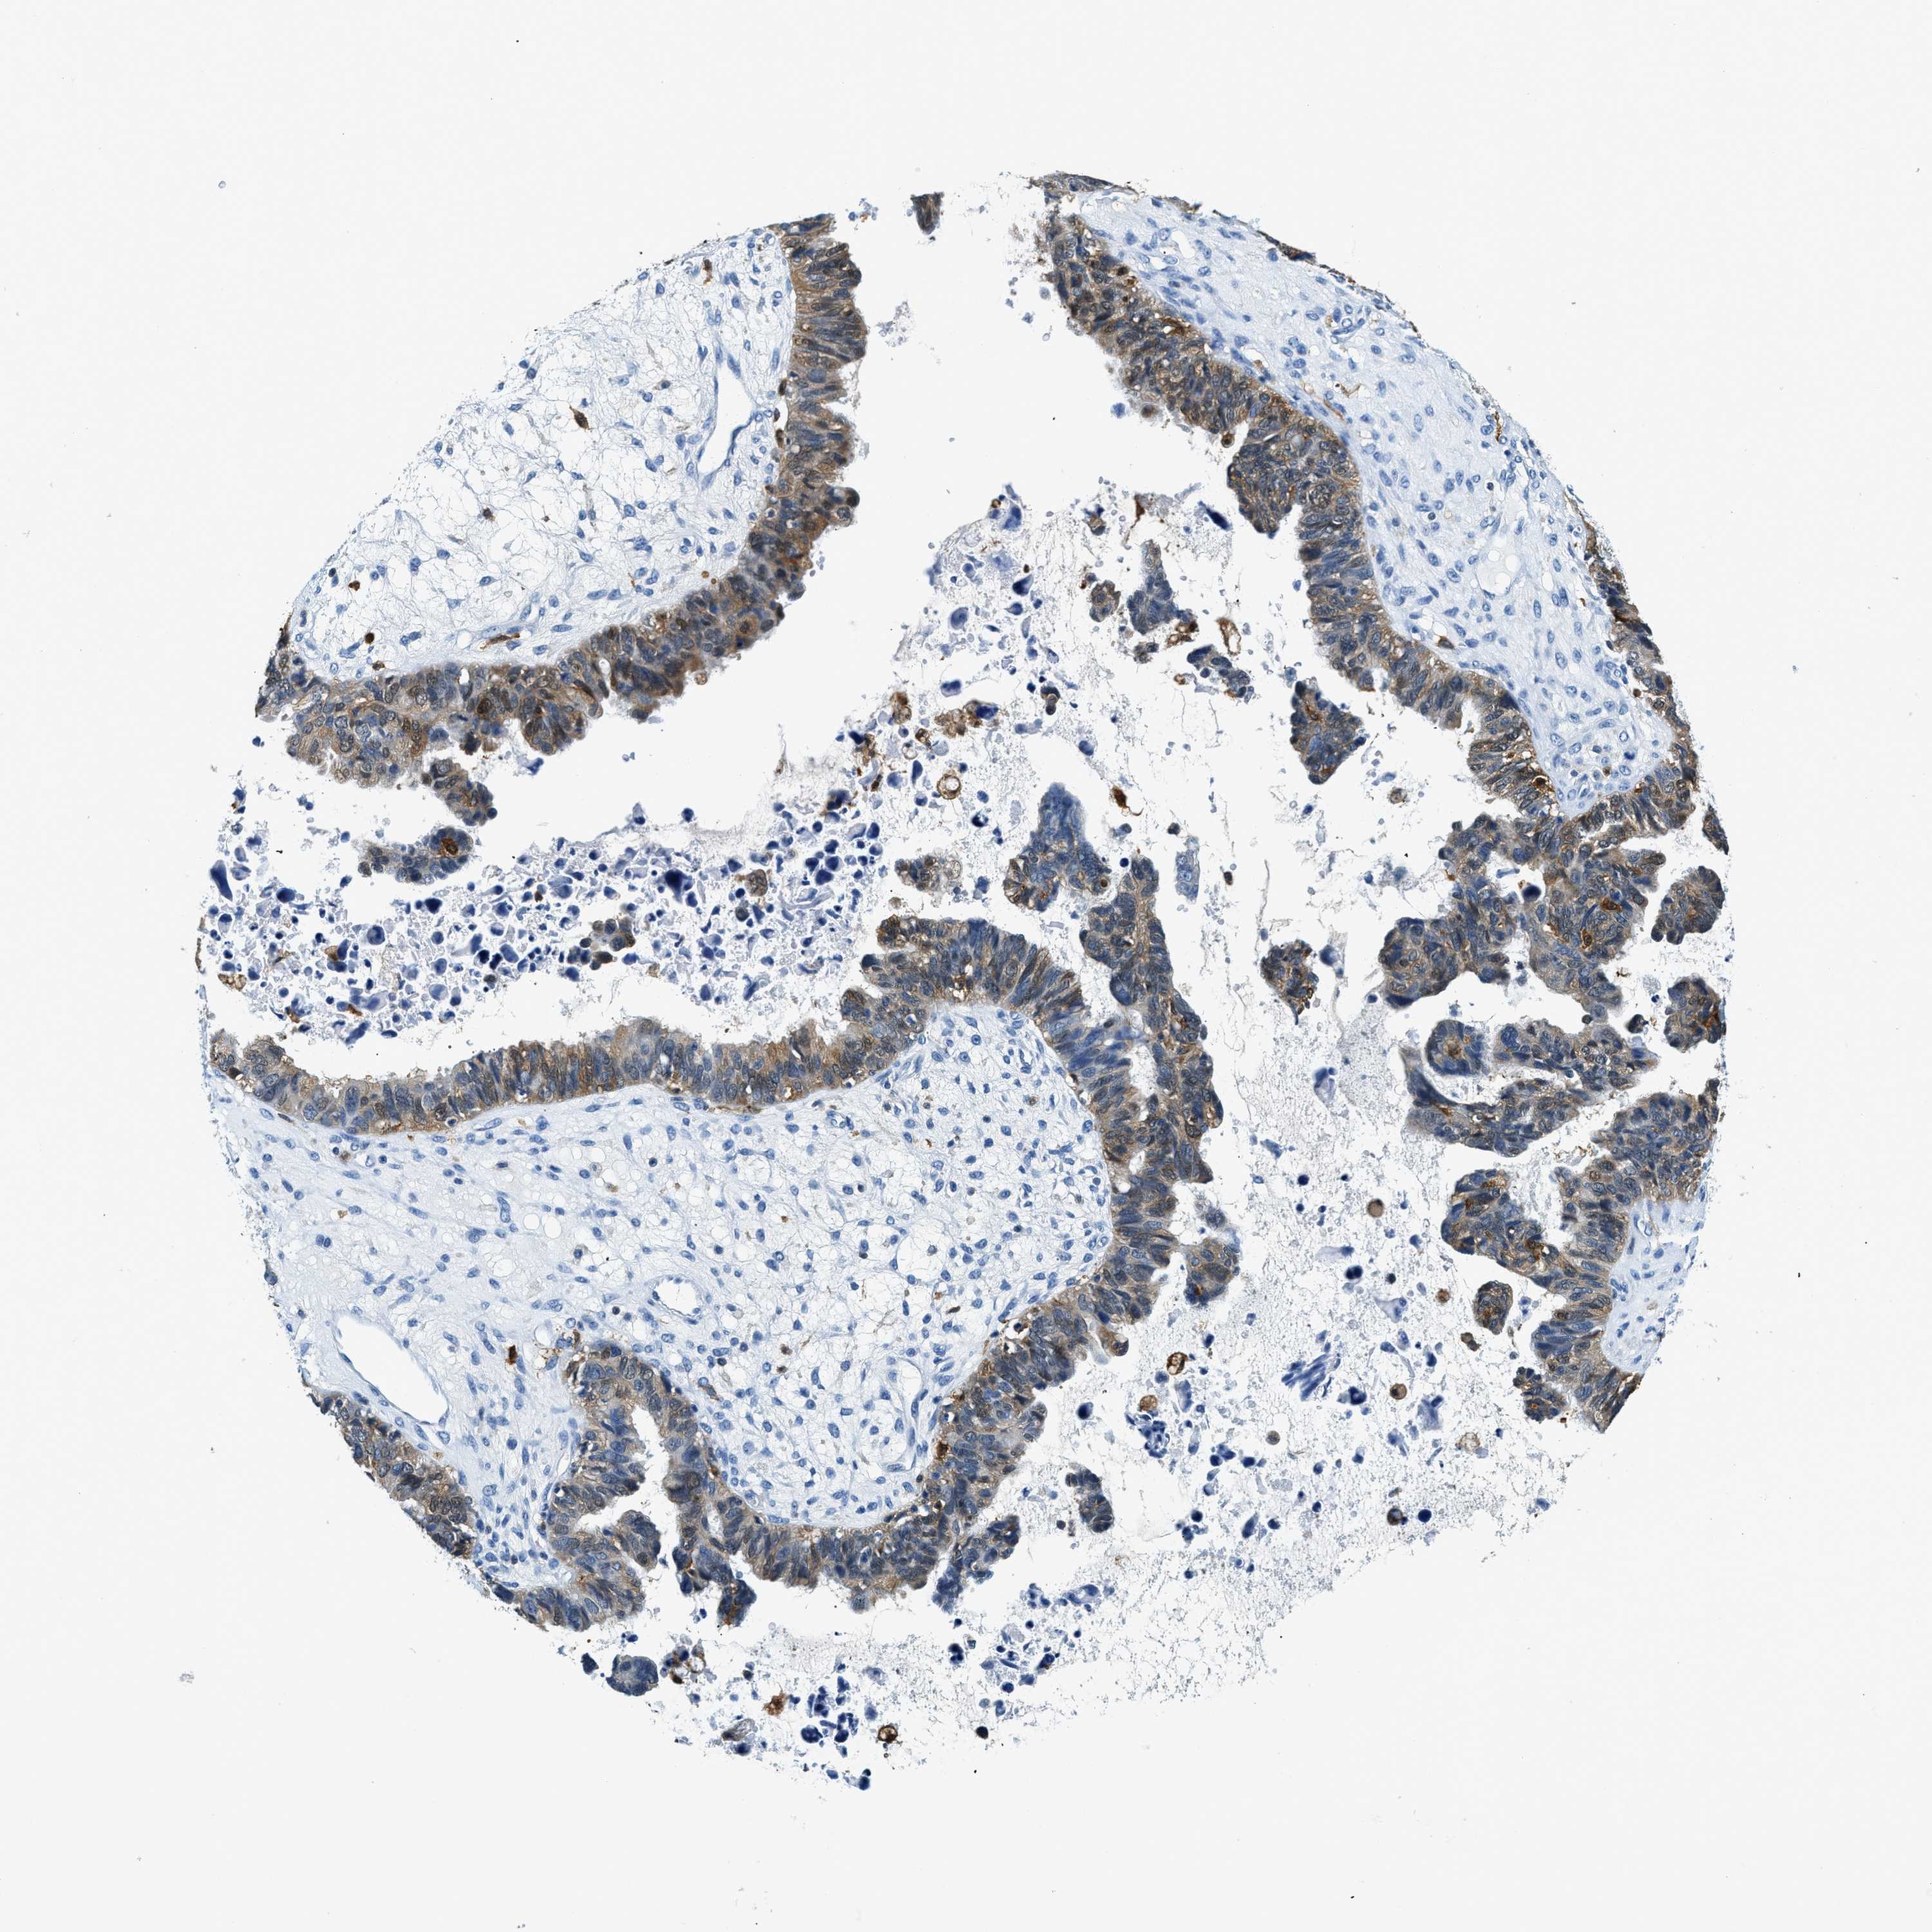

OVARIAN CANCER - Protein expressioni

A mouse-over function shows sample information and annotation data. Click on an image to view it in a full screen mode. Samples can be filtered based on level of antibody staining by selecting one or several of the following categories: high, medium, low and not detected. The assay and annotation is described here.

Note that samples used for immunohistochemistry by the Human Protein Atlas do not correspond to samples in the TCGA dataset.

Antibody stainingi

Antibody staining in the annotated cell types in the current human tissue is reported as not detected, low, medium, or high, based on conventional immunohistochemistry profiling in selected tissues. This score is based on the combination of the staining intensity and fraction of stained cells.

Each image is clickable and will lead to virtual microscopy that enables deeper exploration of all samples and also displays staining intensity scores, fraction scores and subcellular localization as well as patient and tissue information for each sample.

Antibody HPA018843

Antibody HPA019080

Antibody HPA019092

Staining

High

Medium

Low

Not detected

Intensity

Strong

Moderate

Weak

Negative

Quantity

>75%

75%-25%

<25%

None

Location

Nuclear

Cytoplasmic/membranous

Cytoplasmic/membranous,nuclear

Cystadenocarcinoma, serous, NOS

Carcinoma, endometroid

Cystadenocarcinoma, mucinous, NOS

Carcinoma, NOS